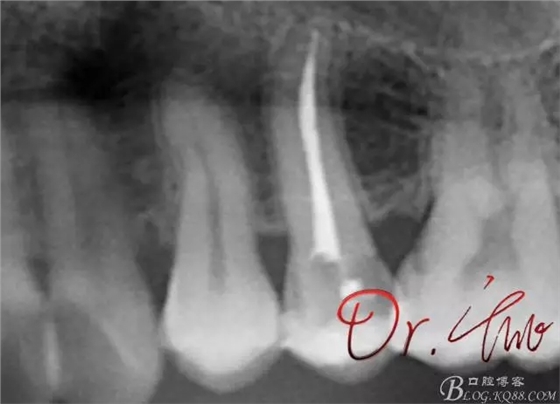

最后根充,明顯可看到臺階位置,期待預(yù)后效果